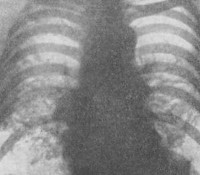

• Рентген, КТ легких. Рентгенологические симптомы легочного сифилиса различны. В исследовании можно найти отдельные очаги с лучистым контуром, множество инфильтратов разных размеров, распространение проса. Коллапс десны вызывает образование полости. Характерно расширение корней легких, грубая деформация рисунка легкого, утолщение плеврального междоузлия.

Легочные инфильтраты с лучевым сиянием рентгенологически неотличимы от онкологической патологии, разлагающуюся гумму можно принять за абсцесс или полость, сифилитическое распространение трудно отличить от туберкулеза. Для целей дифференциальной диагностики проводится анализ мокроты на наличие микобактерий туберкулеза. Пациентам часто нужна консультация врача-фтизиатра, онколога, торакального хирурга.